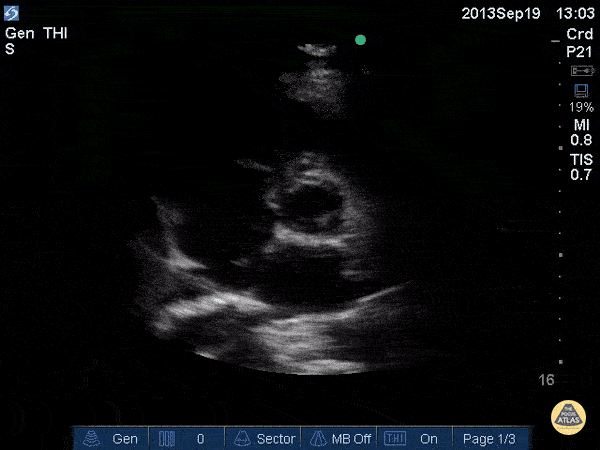

Normal Cardiac Anatomy - Aortic Valve (Short)